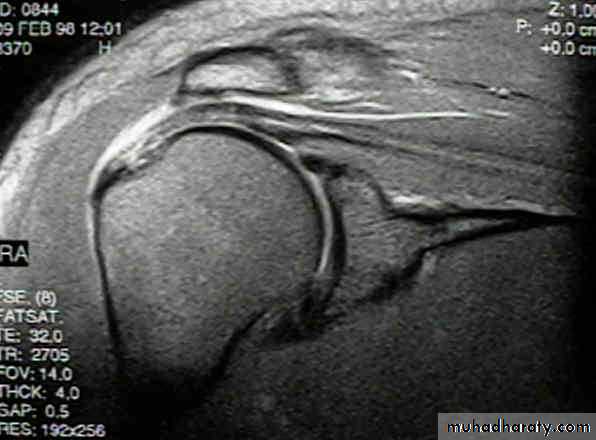

MRI

Best method of diagnosis. It shows the cuff tearUltrasound